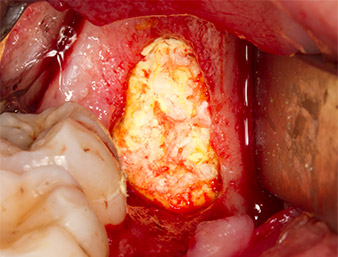

Con el fin de obtener material autógeno para el tratamiento posterior de la herida, se utilizó un inserto piezoquirúrgico (Piezomed B5) para obtener virutas de hueso sano del entorno del resto radicular (figura 5).

El tejido autógeno se extrajo con la punta de trabajo en forma de pala del inserto y se guardó en solución salina fisiológica hasta su posterior utilización (véase figura 13).

A continuación, el tejido óseo autógeno (figura 13) se incorporó en el alvéolo y en el defecto óseo circundante (figura 14). Un velo de colágeno sirvió de protección para el nervio expuesto y cubrió las virutas óseas hasta el nivel del hueso (figura 15). Se aplicaron puntos de sutura con hilos Vicryl de grosor 4.0, que cerraron los tejidos blandos abiertos (figura 16). Tras la operación, se prescribió un preparado de ibuprofeno (Seractil 400 mg 3x1) y un antibiótico con amoxicilina y ácido clavulánico (Augmentine 1g 2x1).